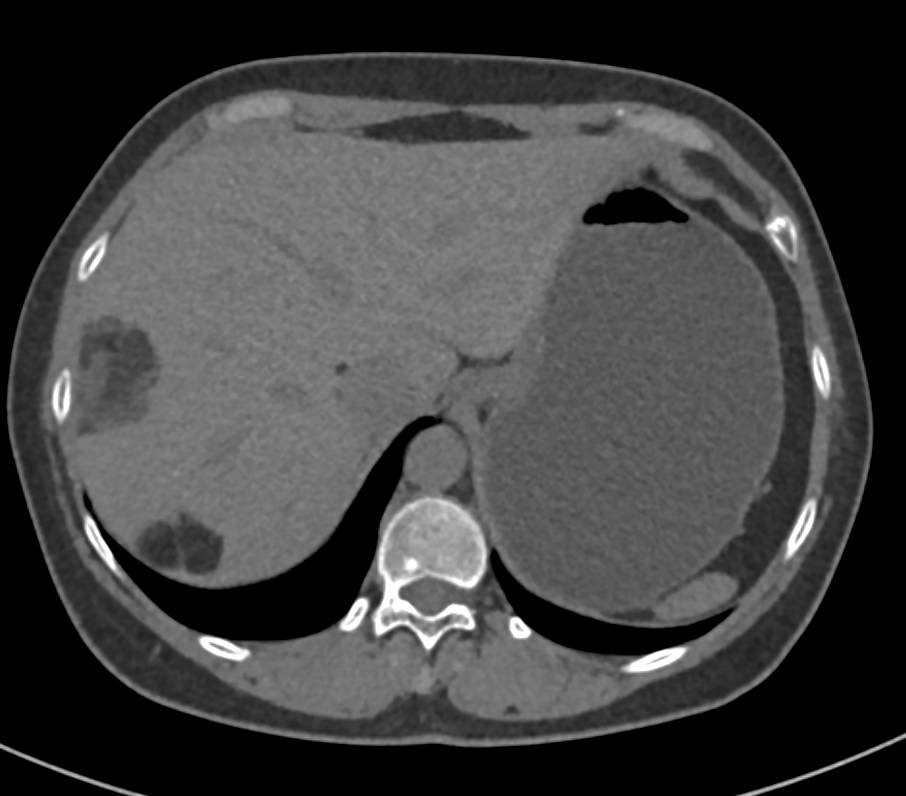

Necrotic Liver Metastases